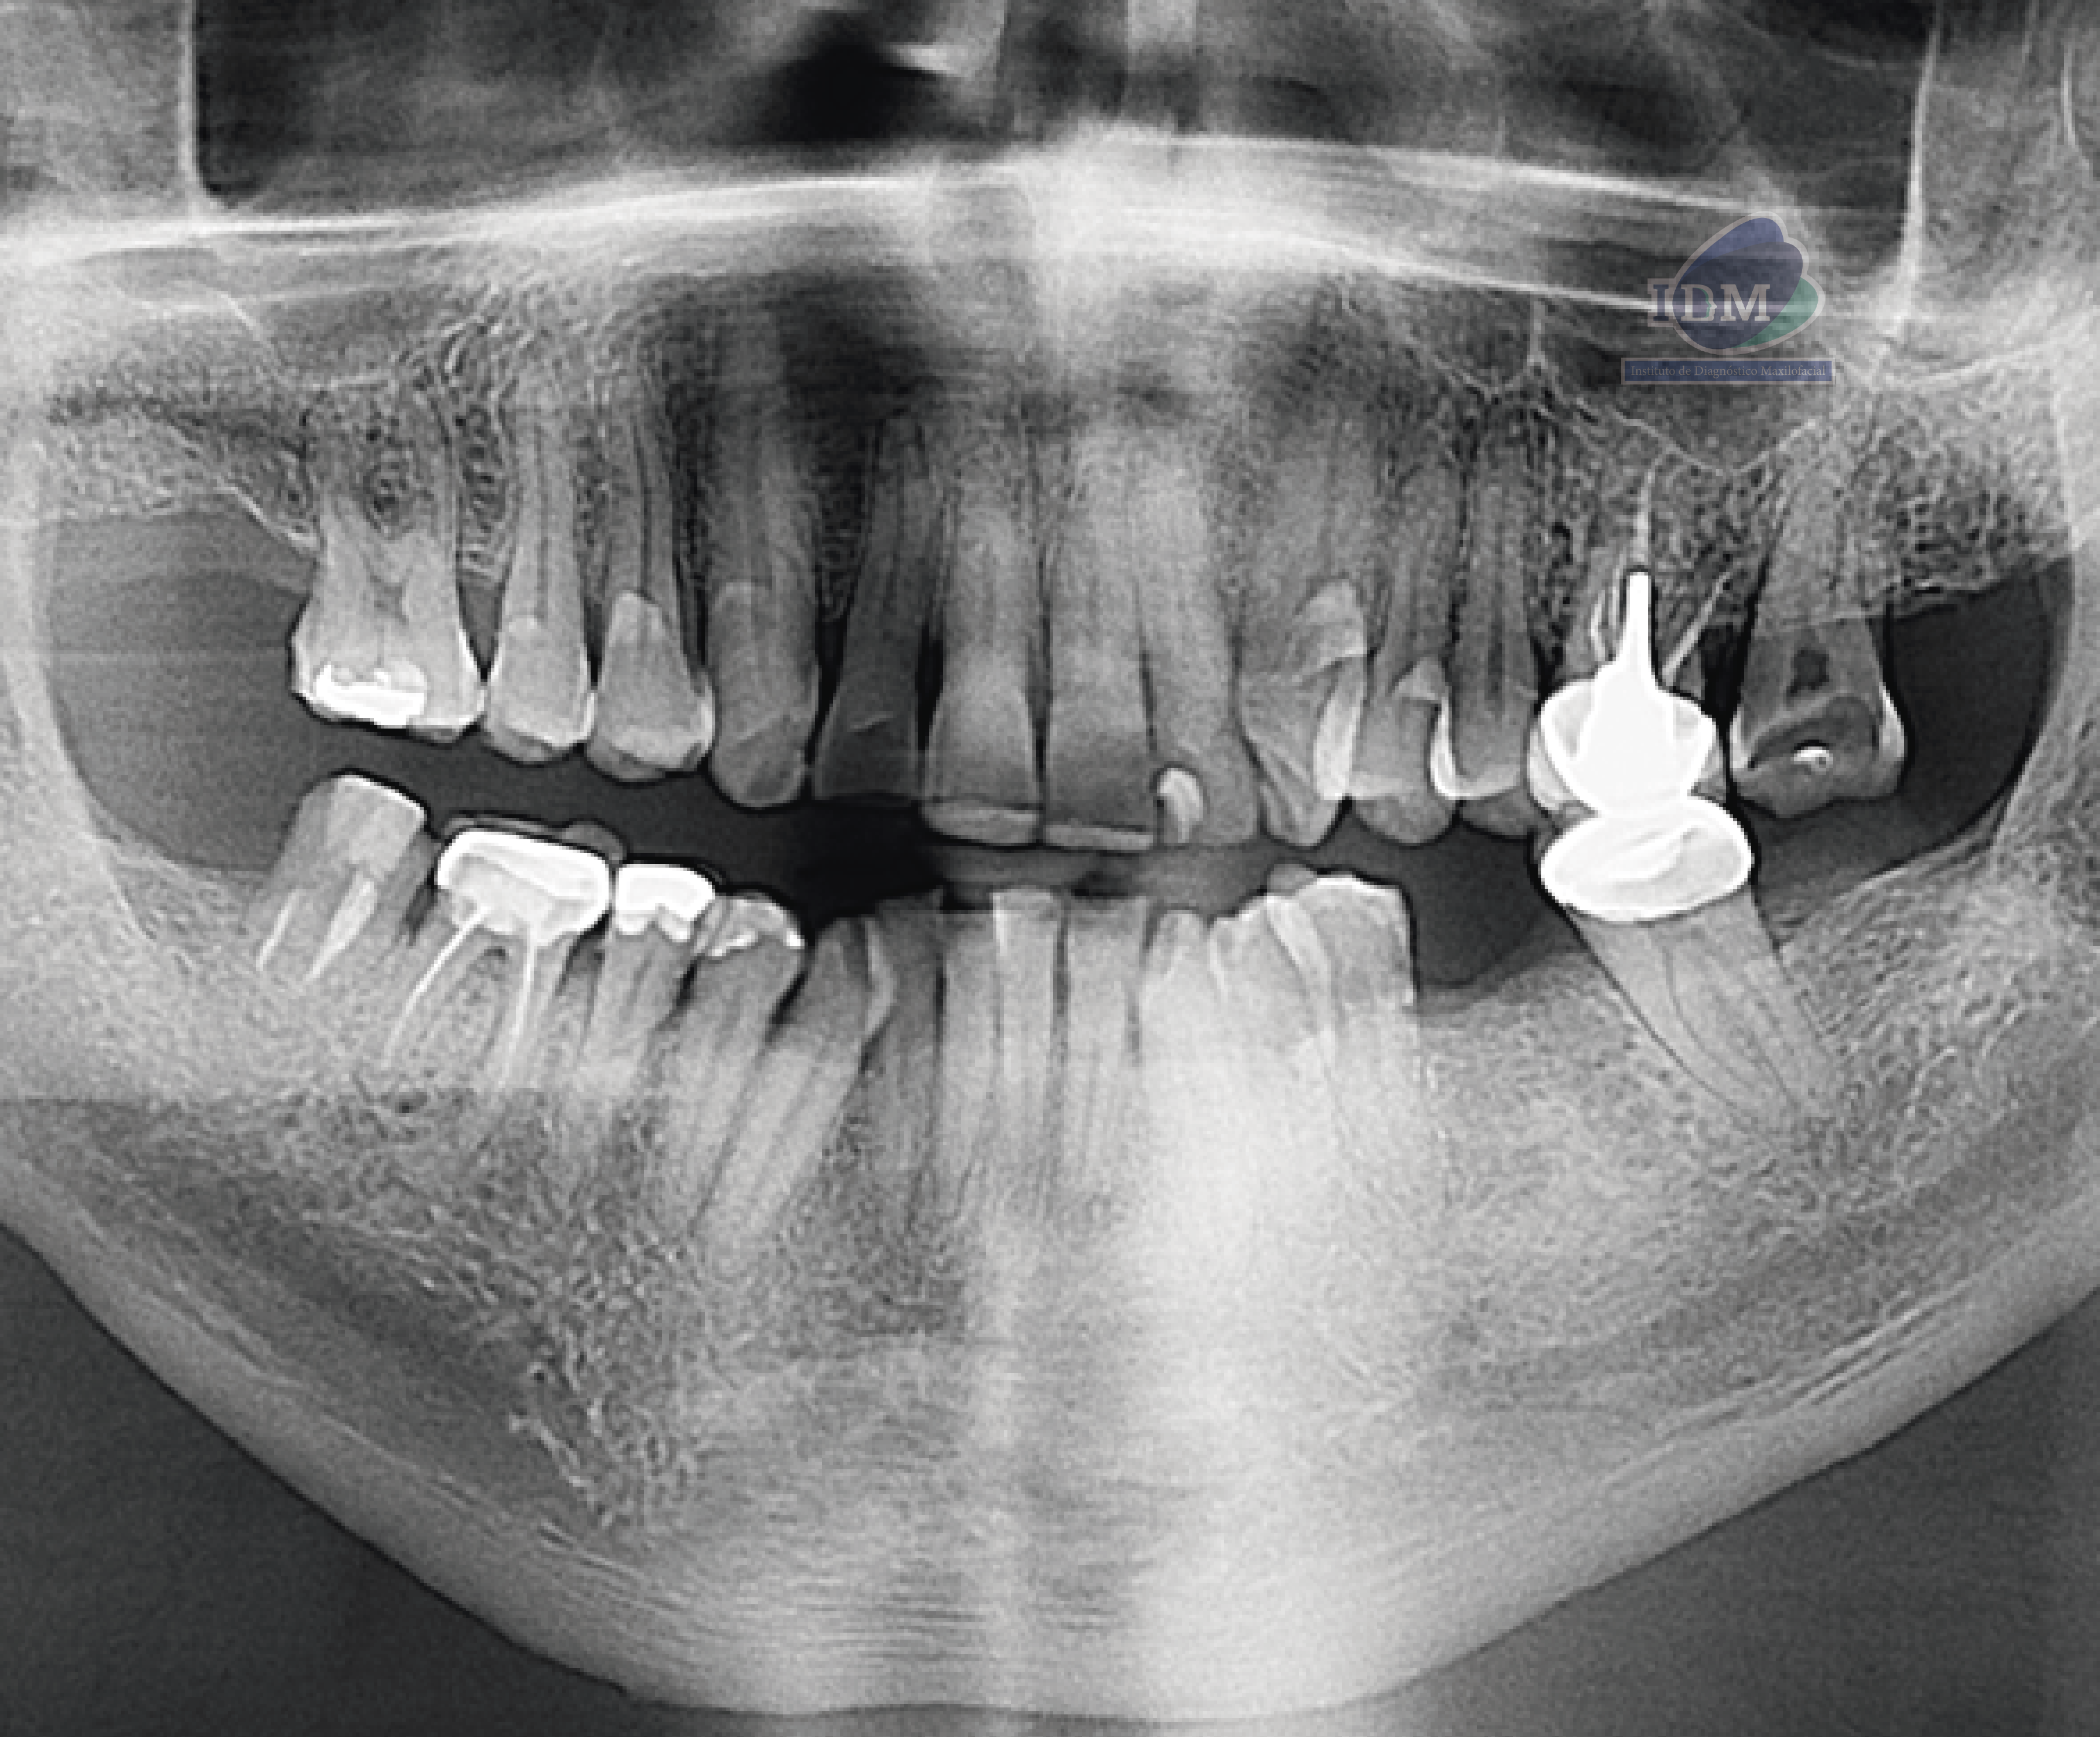

Radiografia Panorámica

En la radiografía panorámica se evidencia aplanamiento de ambos cóndilos mandibulares con acentuación bilateral de las escotaduras antegoniales. En el cóndilo mandibular izquierdo se observa esclerosis acompañada de imágenes radiopacas circundantes, compatibles con cuerpos óseos libres.